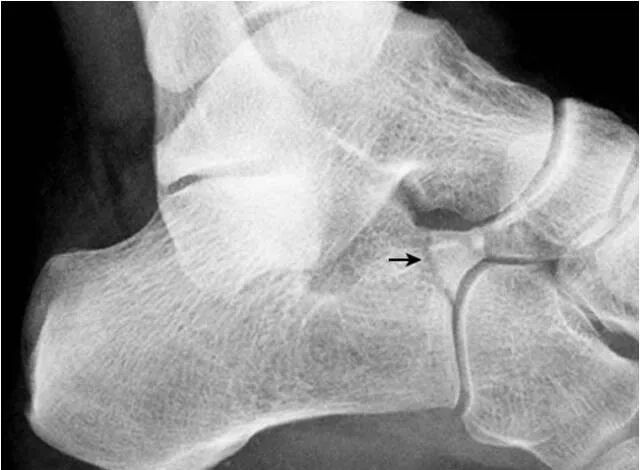

7.跟骨副骨:

位于距骨、跟骨、舟骨及骰骨所围成的间隙内,呈小的骨性突起(箭头),为正常变异。需与跟骨前缘的撕脱骨折鉴别。CT 矢状面重建图像清晰显示该副骨与各骨的关系。